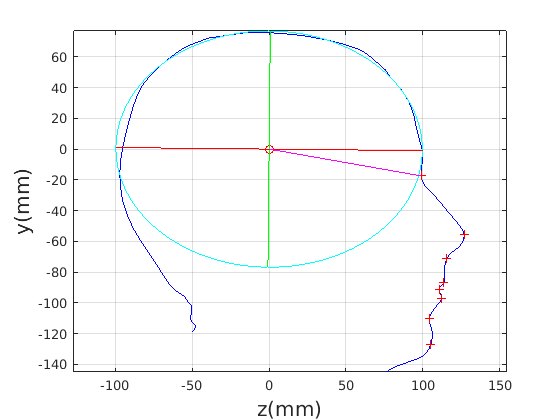

Figure 16 shows examples of the robust ellipse fit for four head profiles. The centre of the ellipse is used in a pose normalisation procedure where the ellipse centre is used as the origin of the profile and the angle from the ellipse centre to the nasion is fixed at -10 degrees. We call this Ellipse Centre - Nasion (ECN) pose normalisation and later compare this to GPA. The major and minor axes of the extracted ellipses are plotted as red and green lines respectively in Fig. 16.

|

|

|

|

Figure 17 shows all 100 profiles overlaid with the same alignment scheme. The median value of major ellipse axis and the ellipse centre-nasion angle differ by 3.6 degrees, so that when the nasion angle is fixed at -10 degrees, the median ellipse angle is -6.4 degrees (cf. -7.4 degrees with manual landmarking of the nasion). We noted regularity in the orientation of the fitted ellipse as is indicated by the clustering of the major (red) and minor (green) axes in Fig. 17 and the histogram of ellipse orientations in Fig. 18. For most people, the major axis of the ellipse is closely aligned with the y-axis (upright), and titled slightly forwards. A minority of heads (9%) in the training sample have their major ellipse axes closer to the vertical (these relatively tall and short heads are known as brachycephalic.) Ellipse axis clustering (relative to the fixed ellipse centre-nasion line) does not appear to be sharply defined. This is because many crania are close to circular in cross-section, making the orientation of these angles sensitive to small changes in shape from one person to the next. Note also the variation at the back of the head due to a variety of hair styles, some of which protrude from under the cap. We limit the region over which we model the cranial shape in order to crop this unwanted data out.